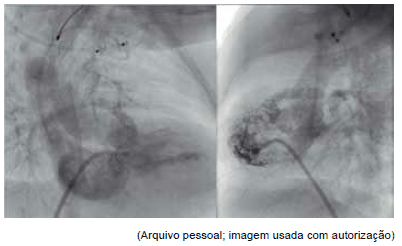

Observe as seguintes figuras de cateterismo cardíaco para responder à questão.

Com relação às figuras, o diagnóstico mais provável da cardiopatia congênita é:

Observe as seguintes figuras de cateterismo cardíaco para responder à questão.

As seguintes figuras de cateterismo cardíaco dizem respeito ao procedimento percutâneo: colocação de